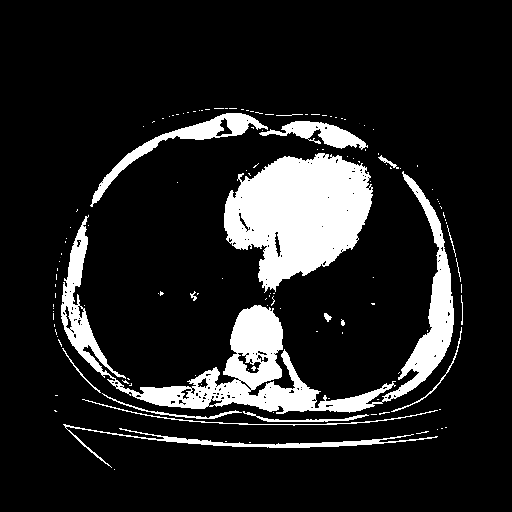

Image Grid

4Γ—3 grid: Rows show different image types (Original NATIVE, Reconstructed NATIVE, Original VENOUS, Generated VENOUS), Columns show windowing techniques (No Window, Lung Window, Mediastinum Window)

Reconstructed NATIVE CT scan (cycle consistency)

Full window (WL 1023.5, WW 4095 β†’ Low βˆ’1024, High +3071)

Actual HU range: [-1024.0, 3071.0]